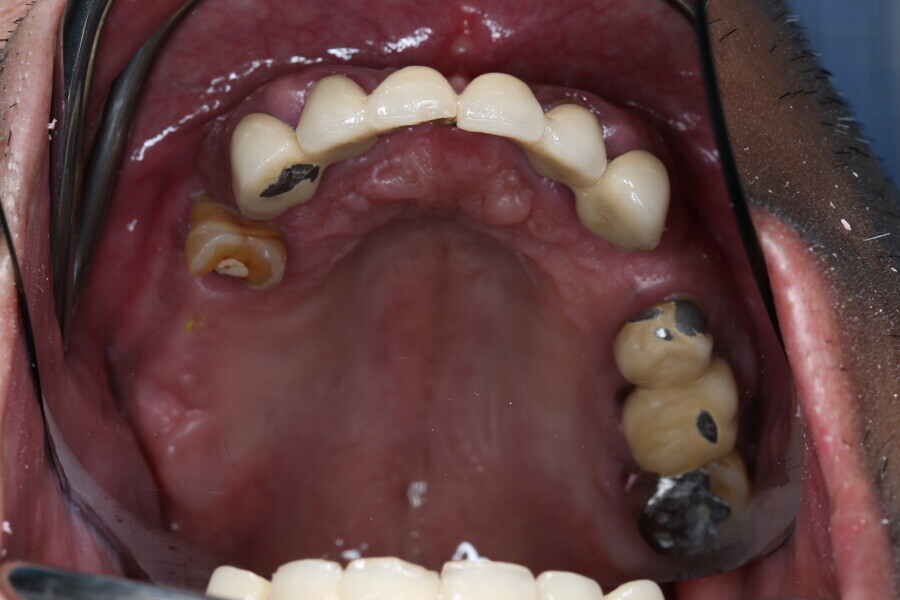

Compromised maxillary dentition treated with Straumann Pro Arch and a digital workflow